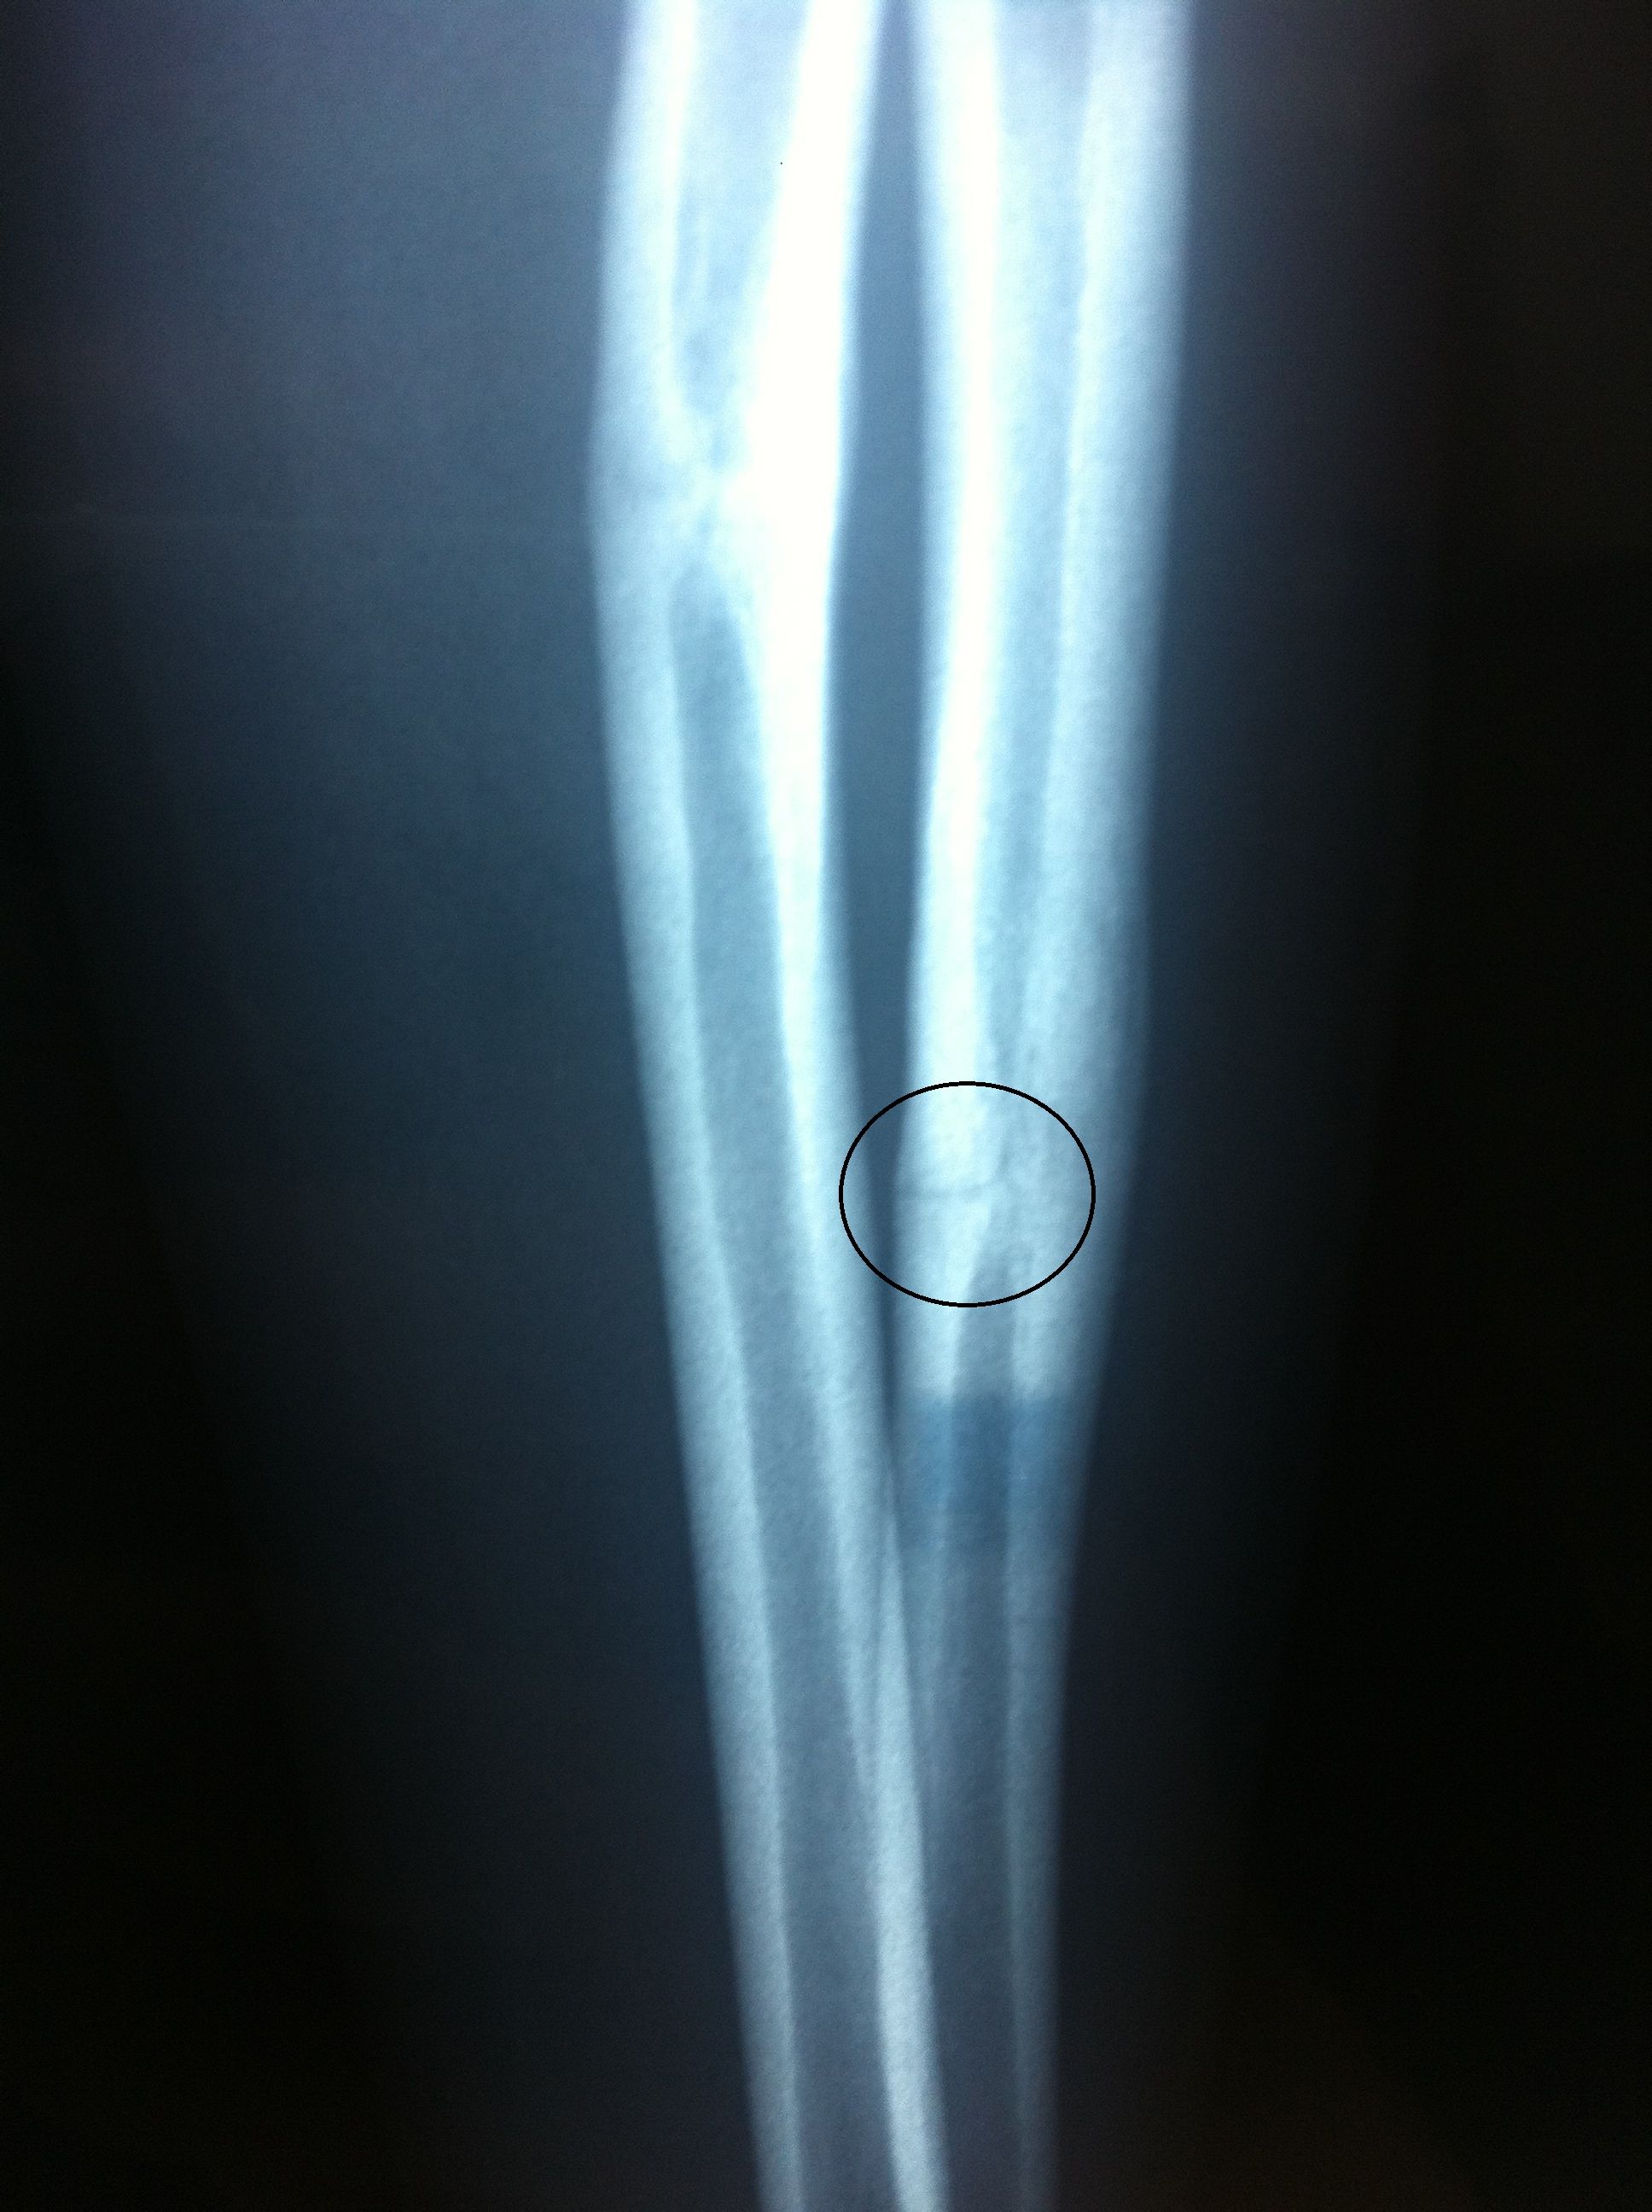

证券之星消息,根据天眼查APP数据显示天智航(688277)新获得一项发明专利授权,专利名为“手骨骨折处置钉通道的智能化规划方法和装置”,专利申请号为CN202010099627.2,授权日为2024年12月6日。

专利摘要:本公开涉及一种手骨骨折处置钉通道的智能化规划方法和装置,该方法通过获取骨折手骨的目标图像;接收用户在该目标图像中指定的断裂骨骼区域;对该断裂骨骼区域进行膨胀和腐蚀处理,以将该断裂骨骼区域分离成两个孤岛状区域;根据两个该孤岛状区域通过预设通道确定策略确定待定置钉通道;从该待定置钉通道中确定目标置钉通道。这样,通过获取骨折手骨的目标图像,并通过预设通道策略确定待定置钉通道,并从该待定置钉通道中确定目标置钉通道,能够在以图像数据为依据的前提下准确确定置钉通道,实现置钉通道的智能规划,能够提高置钉通道规划的可靠性,降低人工确定置钉通道的风险系数,也能够避免对医生经验的过分依赖。